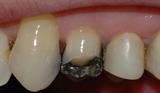

![]()

Bildet viser en jeksel i underkjeven med en stor amalgamfylling. Det går en tydelig bruddlinje langs den ene tyggeknuten.